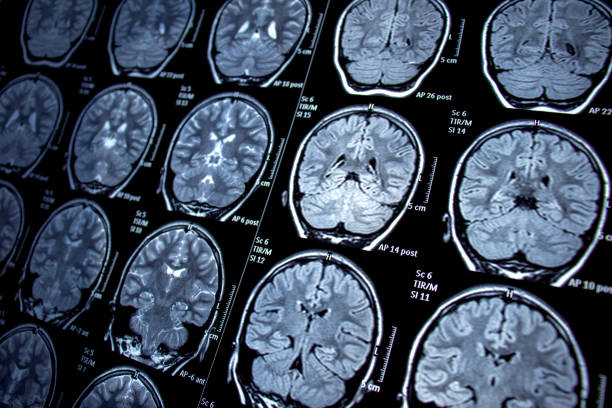

圖1:癲癇的主要潛在病理生理學(xué):神經(jīng)層面的異常興奮和抑制信號。

干細胞可以改善信號通路的這種不平衡,同時(shí)促進(jìn)癲癇發(fā)作后大腦的修復。